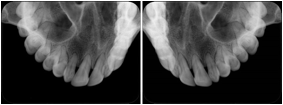

1. A patient in rural Canada visits a general ophthalmologist and is found to have diabetic macular edema. The general ophthalmologist would like to discuss the case with a retina specialist before performing laser surgery. A fluorescein angiogram is done with multiple retinal images taken in a timed series after an intravenous injection. The images along with a Structured Display are shared via a Health Information Exchange with a retina specialist in Calgary, who opens them using his Ophthalmology EMR software and consults via phone with the general ophthalmologist. Both physicians view the images in the same layout so the retina specialist can provide accurate guidance for treating the patient.

2. A patient in rural Iowa visits his primary care physician for management of diabetes. Three non-mydriatic (patient's eyes are not dilated) photographs are taken of the back of each eye, and forwarded electronically along with a Structured Display to an ophthalmologist in Iowa City. The ophthalmologist reads the photos in an agreed upon layout so there is no mistake about what portion of which eye is being viewed. The ophthalmologist is able to tell the primary care physician that his patient does not need to come to Iowa City for face to face ophthalmologic care, but that there is a particular view of the left eye that should be photographed again in 6 months.

Ophthalmic Retinal Study Structured Display

Figure OO-3. Ophthalmic Retinal Study Structured Display